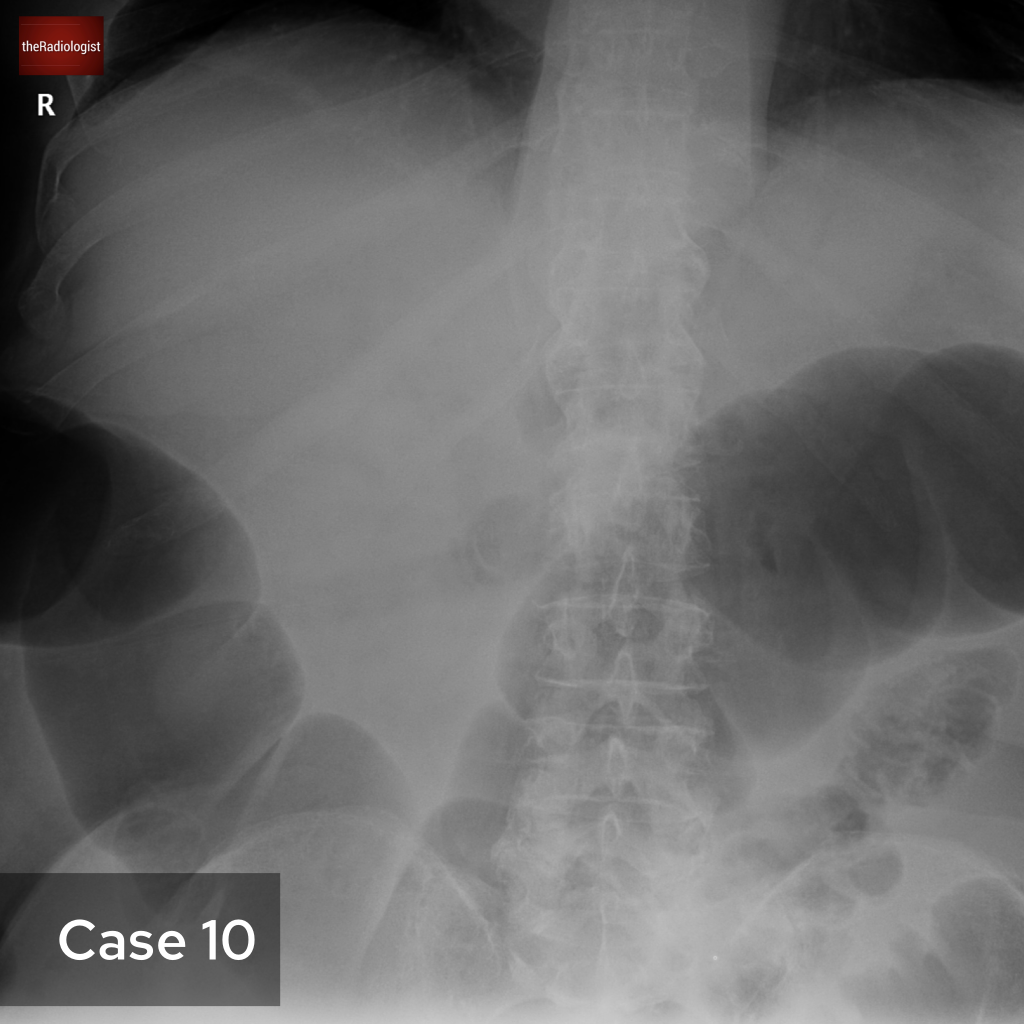

Although we couldn’t see this on our CT case, irregularity of the endplates can be seen after a few weeks on X-Ray and CT as well as loss of disc space. MRI is more sensitive and we are looking for high T2 or STIR signal within the endplates, disc and paraspinal tissues and psoas muscles. Gadolinium contrast can help as we may see enhancement of the endplates, disc and peripheral enhancement of any abscesses. It’s important on MRI to ensure there is no significant central canal stenosis secondary to abscess formation or vertebral collapse.